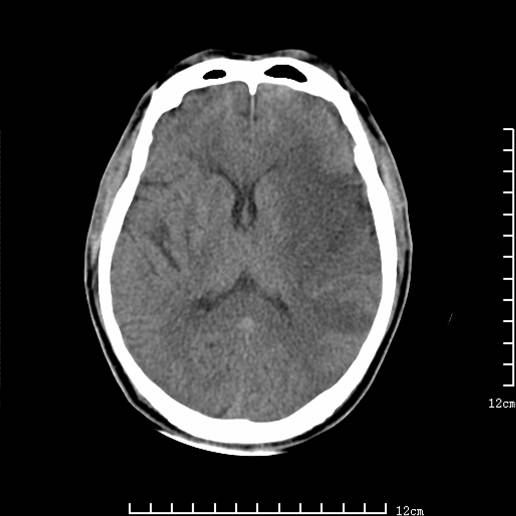

以下图像分别是3月25日凌晨及下午图像、3月27日、4月16日的ct图像。

3月27日

1)左侧额颞顶叶、岛叶及基底节区(相当于左侧大脑中动脉供血区)大面积脑梗塞。2)右侧基底节区腔隙性脑梗塞。

大脑中动脉供血区大面积脑梗塞没有问题。